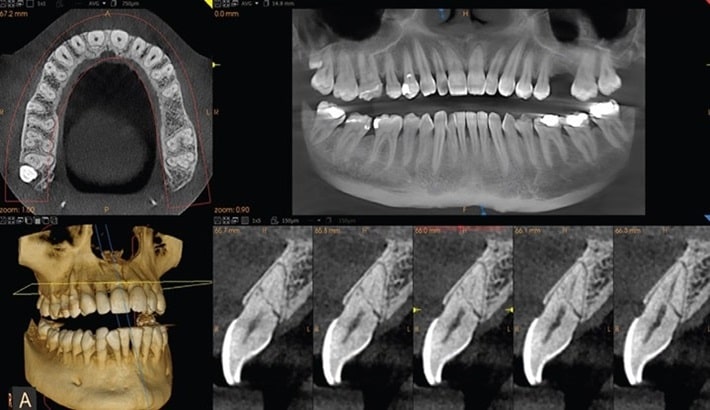

کارکنان دلسوز کلینیک تابا میدانند که آزمایشهای تشخیصی میتواند باعث دلهره و ناراحتی شود و همیشه یکی از همکاران ما در دسترس است تا در مورد سؤالات یا نگرانیها، به شما کمک کند. (تصاویر مجموعه)

رادیولوژیست های ما با تکنسین های آموزش دیده کار می کنند تا تجربه تصویربرداری دلسوزانه و تخصصی را به شما ارائه دهند. رادیولوژیست ها، پزشکانی هستند که پس از اتمام دوره های پزشکی، 4 تا 6 سال آموزش پیشرفته دیده اند و تکنسین های رادیولوژی که از نزدیک با رادیولوژیست ها کار می کنند، 2 تا 4 سال در زمینه فناوری رادیولوژی آموزش می بینند. (معرفی پزشکان) (معرفی کارشناسان)